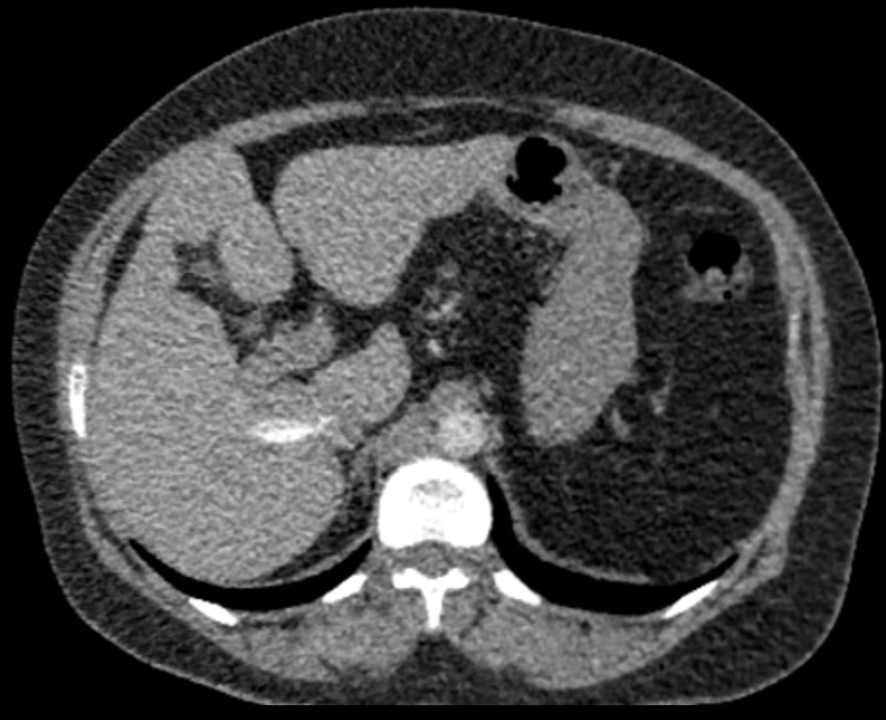

Clinical Case [Uncaptioned image] [Uncaptioned image]

Image Findings: The patient underwent contrast-enhanced computed tomography which showed features of a congested liver with flip-flop pattern of enhancement. Hepatic veins show hypoattenuation on delayed phase. An accessory hepatic vein is also noted in segment VI. A diagnosis of Budd Chiari syndrome (BCS) was made on the basis of the clinical and imaging features. The patient was referred to the interventional radiology team for an endovascular rescue. On conventional venogram, the diagnosis of BCS was confirmed as the hepatic veins were thrombosed. An accessory segment VI hepatic vein was noted draining into the IVC…